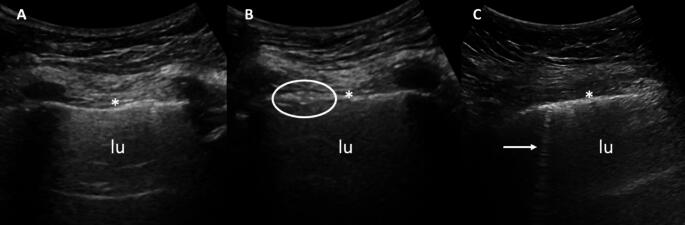

Abstract Image